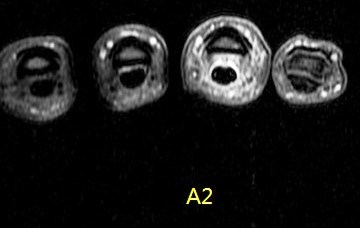

Figure 1 for case A2 pulley rupture finger (RID2437)

Figure 1

A2 pulley rupture finger (RID2437)